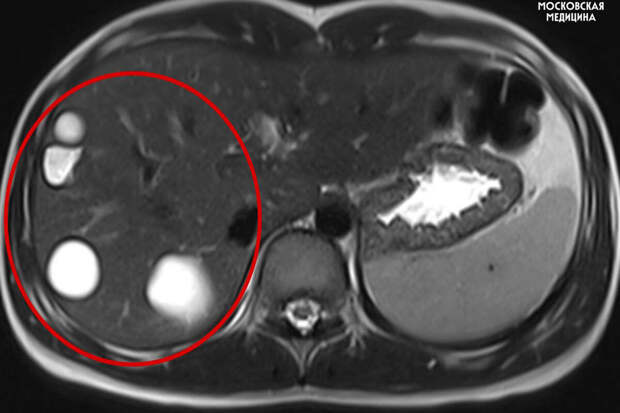

Врачи больницы имени Сперанского спасли 14-летнюю девочку с множеством паразитарных кист в печени. Об этом сообщили в пресс-службе столичного департамента здравоохранения.

Кисты медики обнаружили случайно во время планового обследования. После этого ребенка направили на операцию.

"Как правило, эхинококкоз выявляется на поздних стадиях и чаще всего случайно.

В большинстве случаев симптомы заболевания неспецифичны: боль, кашель, незначительная температура и ощущение тяжести в животе, аллергические реакции", - пояснил заведующий хирургическим отделением №1, профессор Игорь Хворостов.Во время вмешательства специалисты удалили пять кист с использованием лапароскопии. Через пять дней после операции пациентку выписали домой.